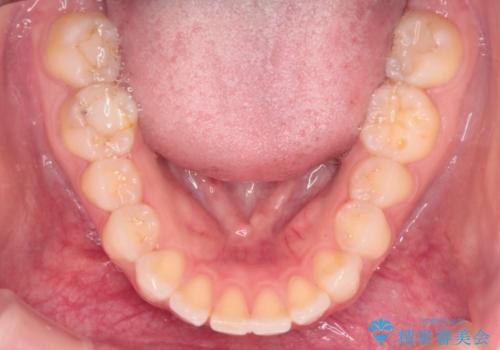

- 治療計画

- 患者様は、上下顎の歯列不正と前歯部の突出感を主訴としてご来院されました。診断の結果、上顎左右第一小臼歯を抜歯することでスペースを確保し、歯列全体を整える方針としました。本来はワイヤー矯正が推奨されるケースですが、患者様のご希望により、透明なマウスピース型矯正装置「インビザライン」を使用した治療計画を立案しました。治療期間は約3年で、奥歯の噛み合わせを維持しながら、徐々に前歯の位置を整えました。

インビザラインは見た目の目立ちにくさと取り外しが可能な点がメリットですが、複雑なケースでは治療計画の精密さが求められます。本症例では奥歯の噛み合わせが崩れないよう注意を払いながら、マウスピースの交換タイミングを細かく設定しました。患者様には装着時間を守っていただくことが重要で、1日20時間以上の装着が必須です。また、抜歯部位のスペースを閉じる過程で、歯の動きが停滞しやすい時期もあるため、定期的なチェックを通じて治療が順調に進むよう管理しました。